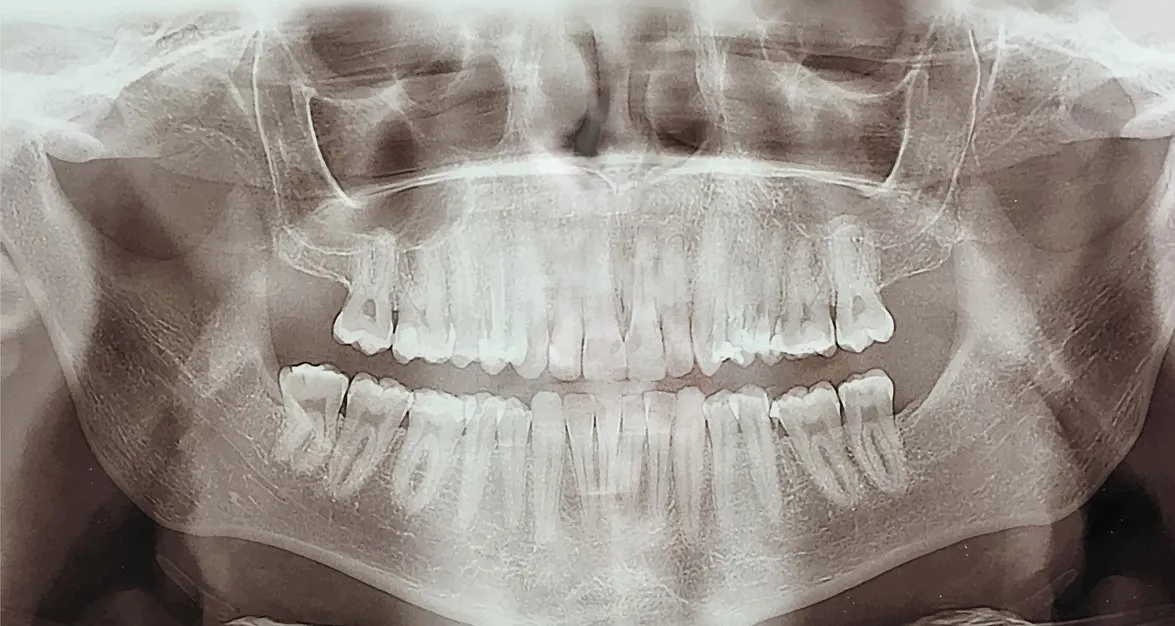

TAC Dentalscan, una nuova tecnologia a disposizione dei pazienti

Si tratta di una nuovissima tecnologia acquisita dalla struttura dedicata alla radiologia dentale che è in grado di eseguire OPT, telecranio, TAC DENTALSCAN e TAC seni paranasali.